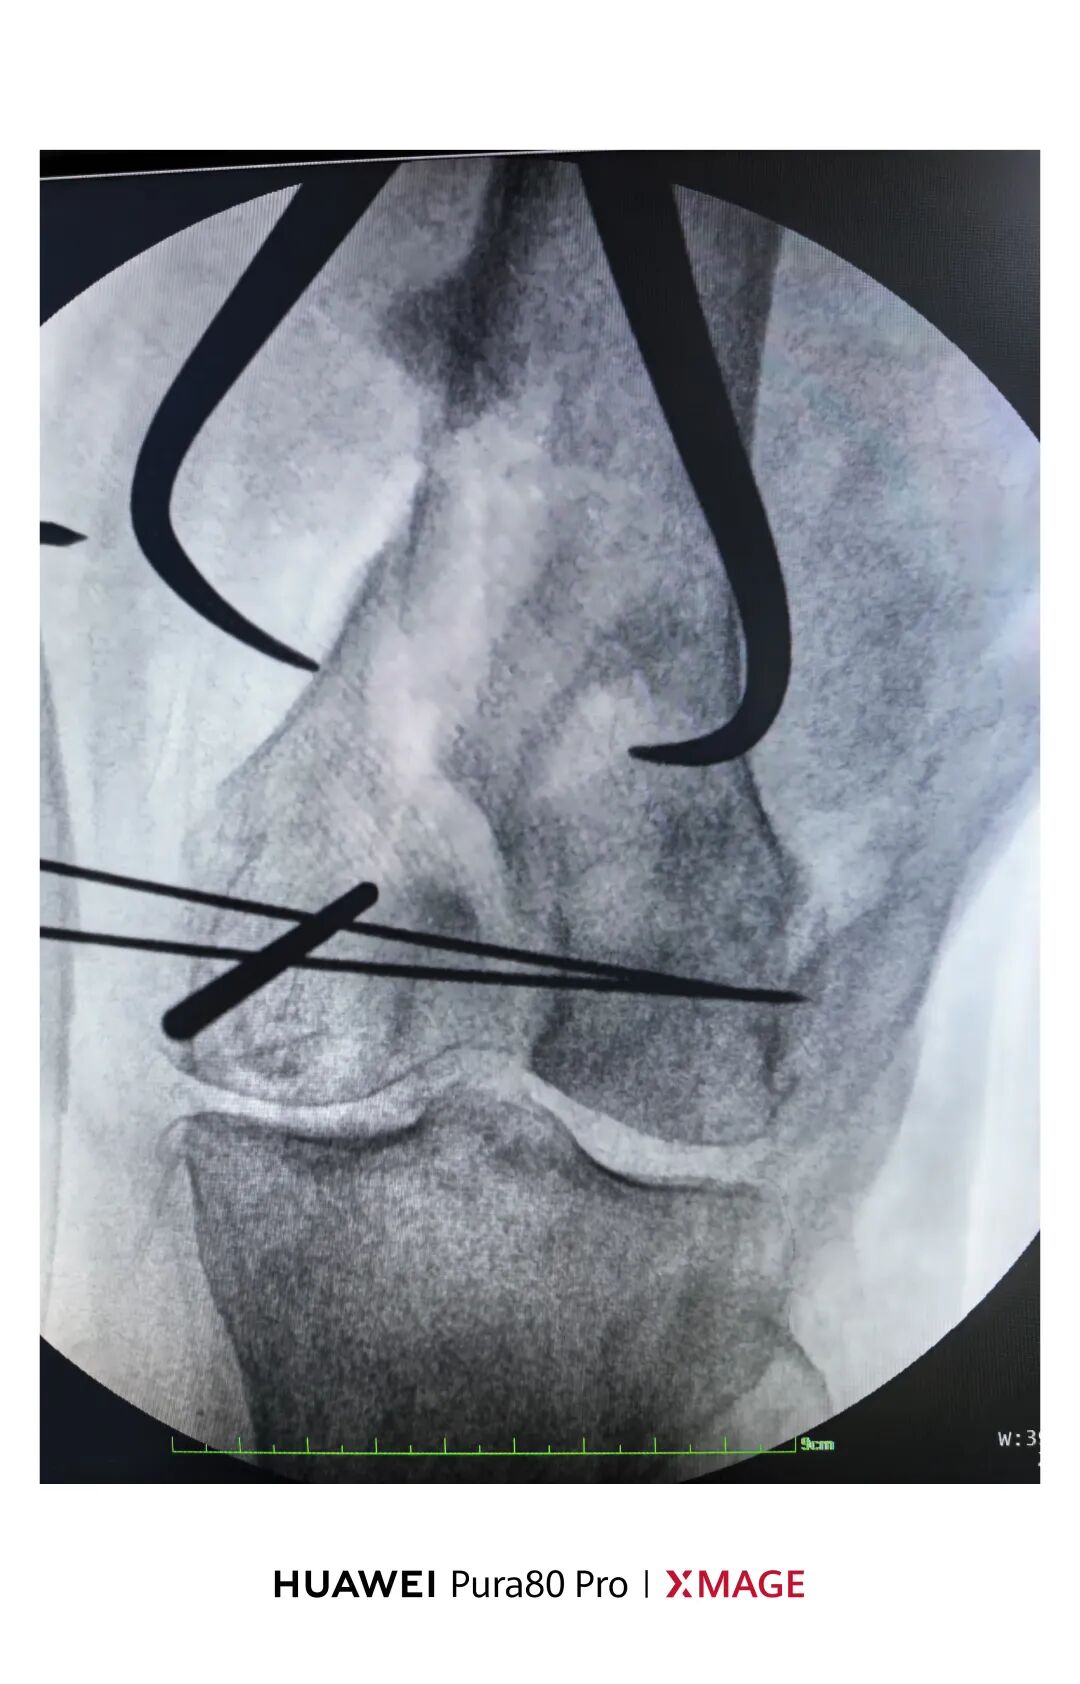

5个月前在魔都骨折,当时建议手术

患者拒绝并签字

给予支具固定

现畸形、疼痛伴活动受限来院

复位满意,力线纠正